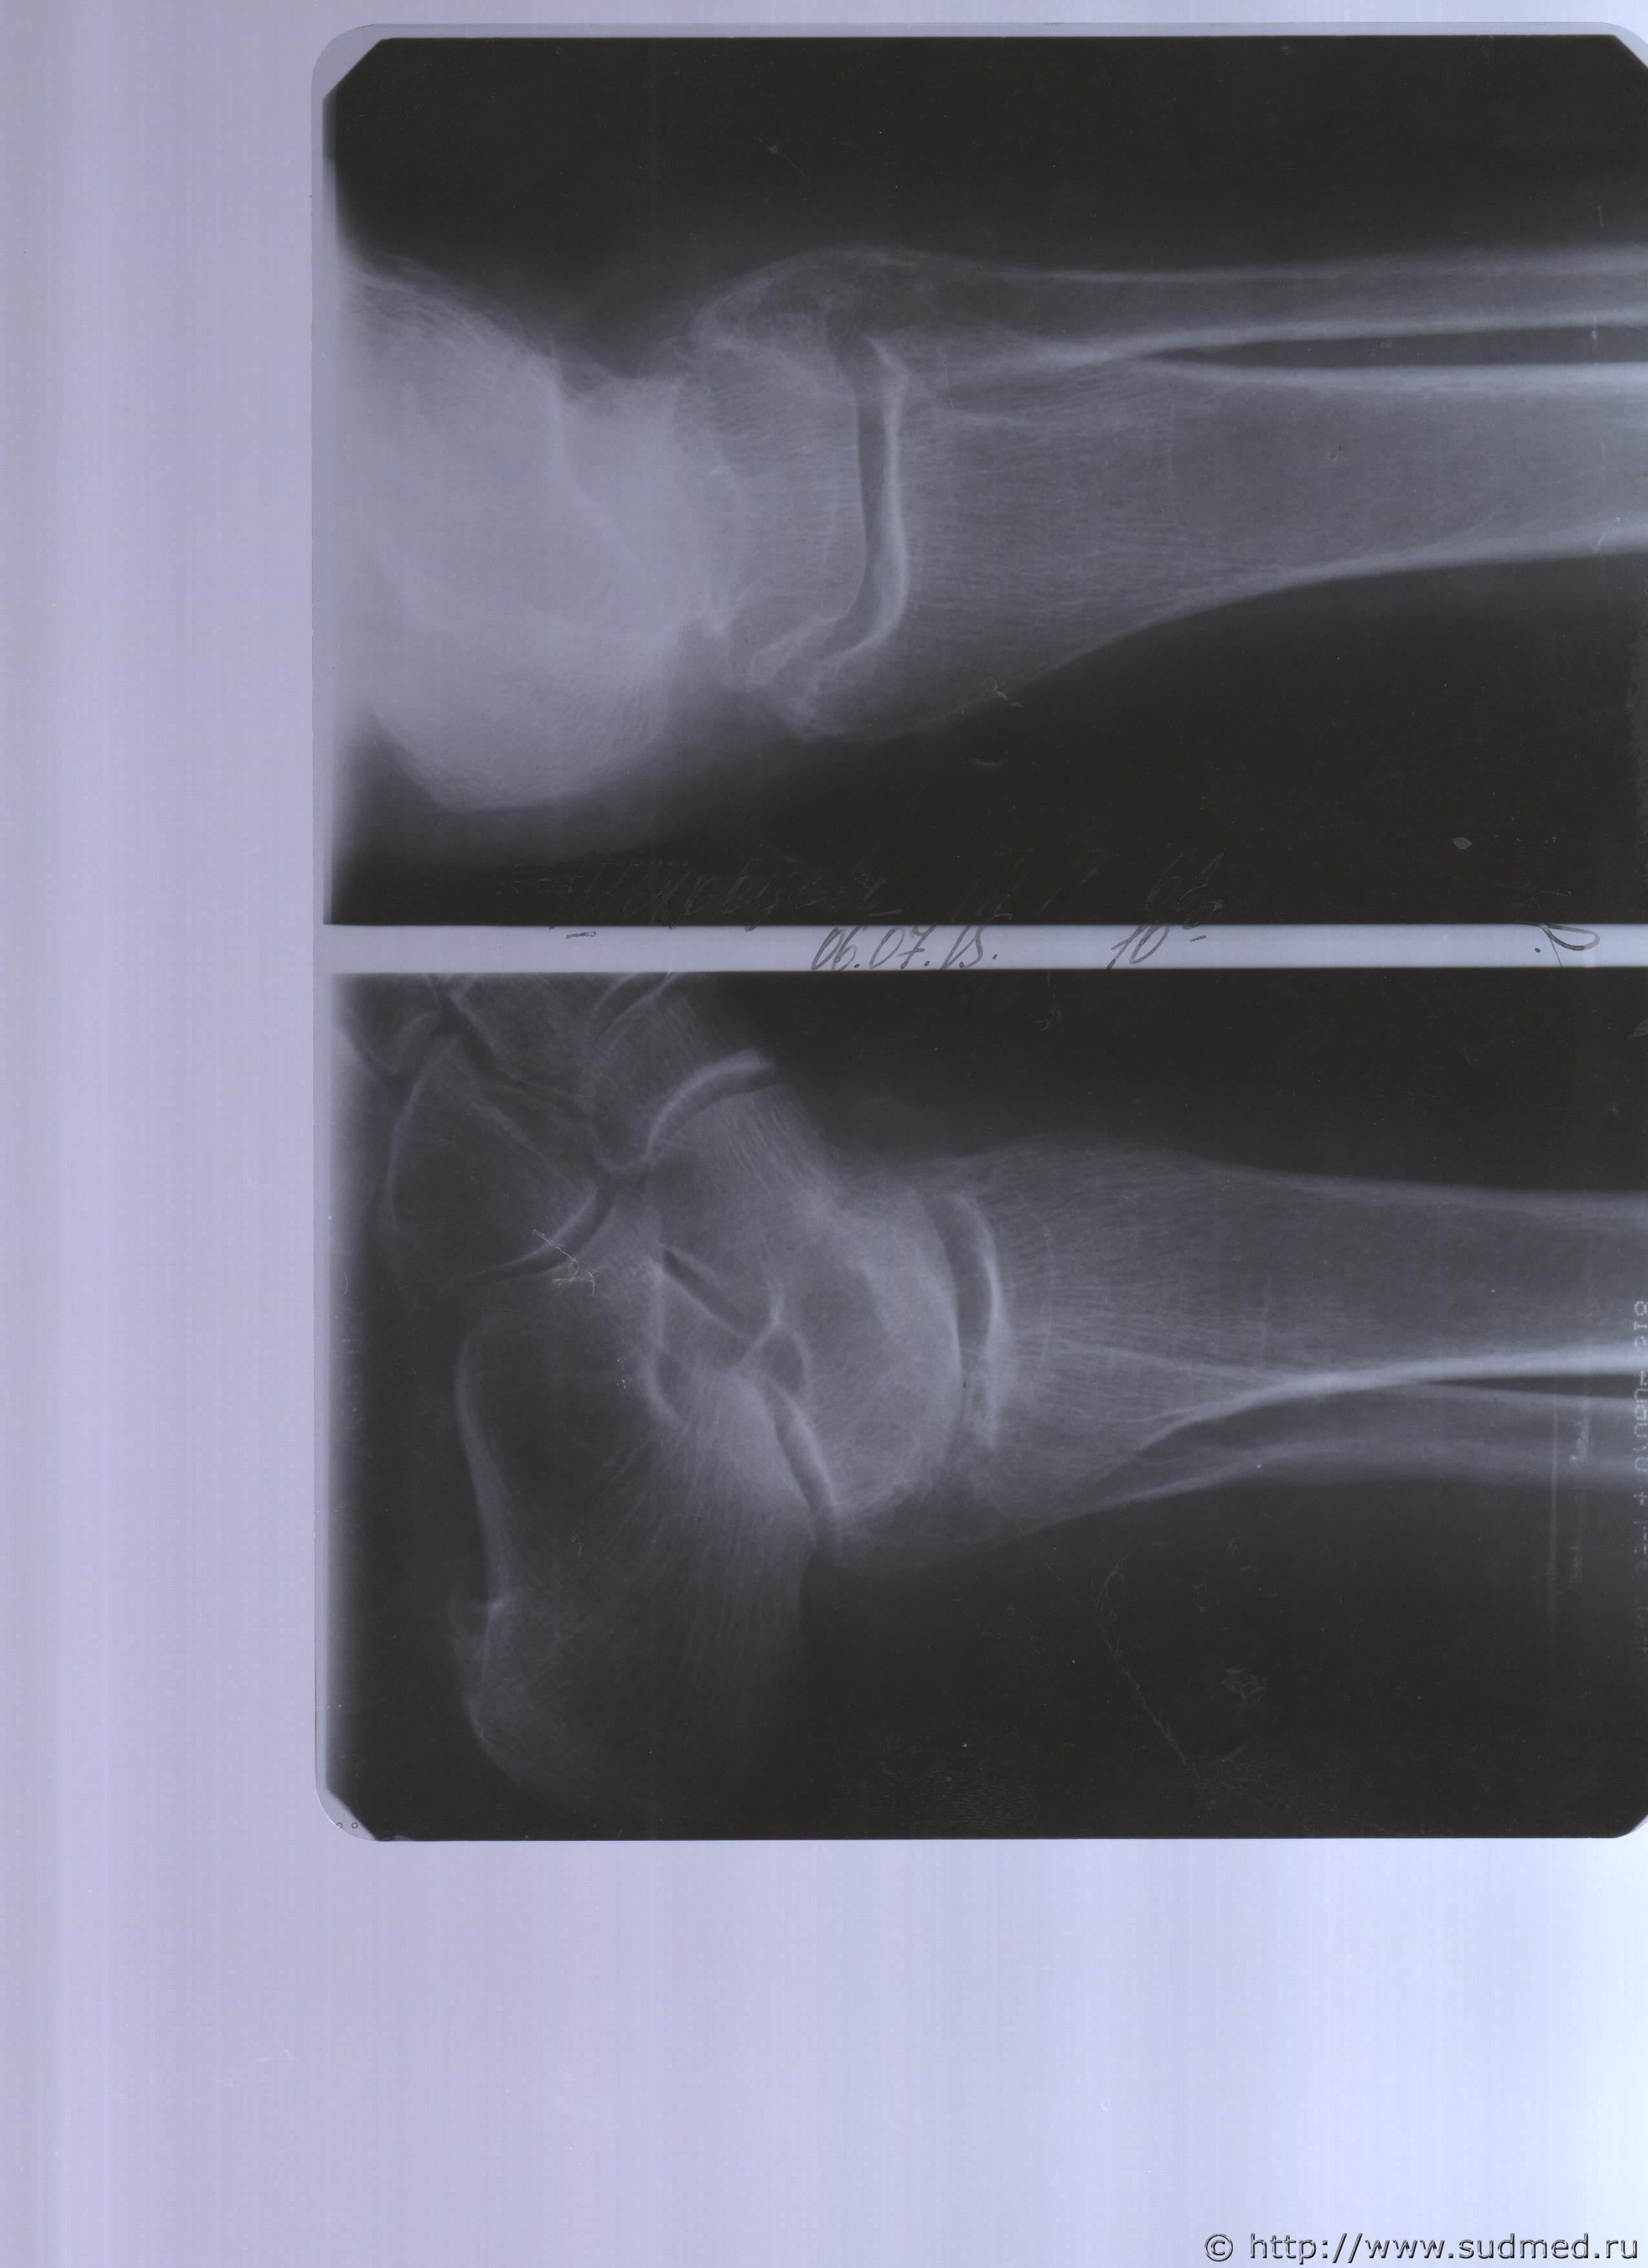

06.07.2015 г. при обращении в горбольницу мне выдали не описанный снимок( все рентгенологи были в отпуске) и справку № 4379 от 06.07.15 г. где диагноз: закрытый 2-х лодыжечный перелом правой голени без смещения. Копию справки прилагаю

За все 12 месяцев, что была на больничном, 8 раз делали снимки травмированной ноги и все заключения именно : «закрытый 2-х лодыжечный перелом правой голени без смещения».

Посмотрите, это снимки за 12 месяцев.

Уважаемая Татьяна! По представленным Вами снимкам ничего сказать нельзя: нет маркировки даты каждого снимка (поэтому, невозможно их сравнивать друг с другом и соотносить с датой травмы), исследование непосредственно пленок гораздо более информативно, чем анализ представленных изображений (детали костной структуры в зоне перелома практически не видны).

Рекомендую проконсультировать все эти снимки у высококвалифицированного рентгенолога. Далее - по ситуации, т.е. в зависимости от его мнения. В любом случае, есть формальные основания для назначения дополнительной экспертизы, т.к., судя по представленному Вами фрагменту заключения эксперта, на экспертизу не были предоставлены все мед.документы с данными о лечении предъявляемой травмы (Вы пишете, что рентгенограммы делались на протяжении 12 месяцев, полагаю, что Вы и врачами наблюдались в течение этого срока, т.е. велась мед.карта).